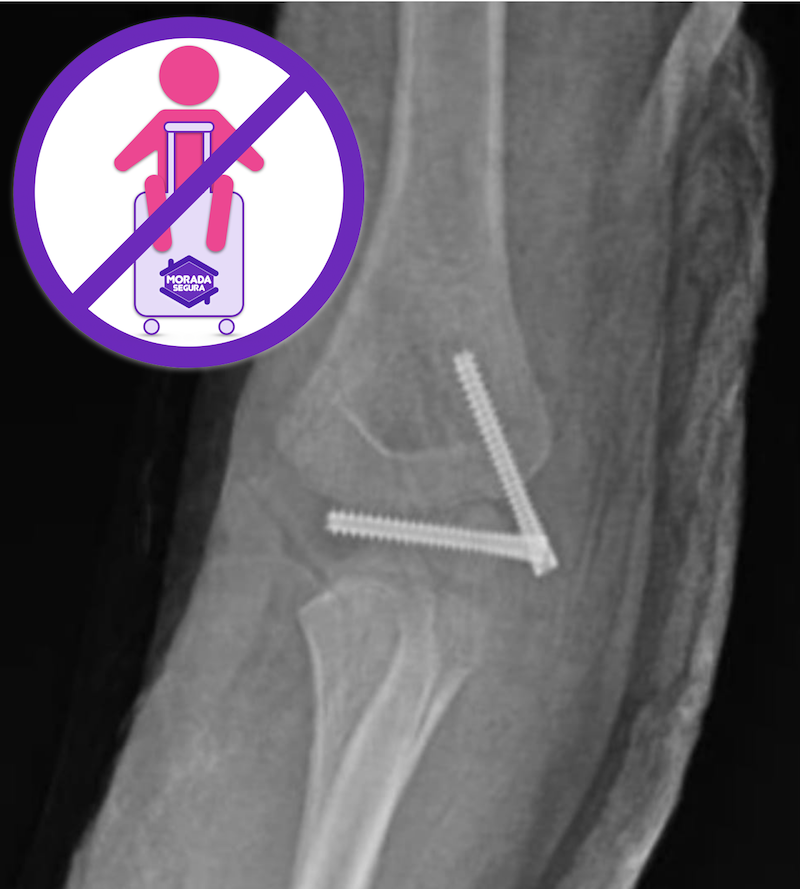

En ese momento la diagnosticaron mal en Montería y me dijeron que solo era un trauma de tejidos blandos, luego en Cali la hice revisar y la operaron de urgencia, ha tenido ya dos cirugías. Debido al mal diagnóstico, habría podido perder la movilidad total del codo, su brazo habría quedado inútil, sin la posibilidad de doblarlo. Gracias a Dios la lleve nuevamente a la clínica. La tuvieron que refracturar, volver a operar y ponerle clavos.

La recuperación ha sido de un año y me habían dicho que no iba a recuperar su movilidad completa. En el momento está mejor gracias a Dios con todo el proceso de rehabilitación, pero el pronóstico era grave porque se le aplastaron dos núcleos de crecimiento del codo. Afortunadamente yo soy fisioterapeuta y por eso se está recuperando tan bien.